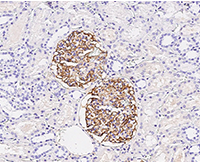

Anti-CR1/CD35, Rabbit pAb: (Cat#: 100464-T08)

Application: IHC-P

Immunochemical staining of human CD35 in human kidney. Image Credit: Sino Biological Inc.